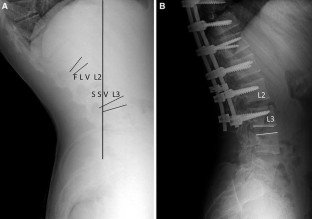

Distal junctional kyphosis (DJK) is a major instrumentation-related complication after the surgical correction of Scheuermann kyphosis (SK). The exact criteria to avoid DJK have been controversial. It has been recommended to include the SSV into the fusion by some authors, while others suggest that fusion to FLV is sufficient. The purpose of this study was to investigate the occurrence of DJK in relation to distal fusion level selection in SK surgery by investigating the relationship between the sagittal stable vertebra (SSV), first lordotic vertebra (FLV), and the lowest instrumented vertebra (LIV).

54 patients (mean age: 21.2 years, range 12–43; male/female: 20/34) with SK who were treated by posterior segmental instrumentation and fusion were prospectively evaluated. Patients were allocated into 3 groups according to distal fusion level. In group 1, SSV was chosen as LIV (n = 20), and in group 2, LIV was the FLV (n = 16). Third group consisted of 18 patients in whom SSV and FLV was the same vertebra. Distal junctional angle, sagittal plane analysis, and clinical outcomes according to SF-36 were evaluated.